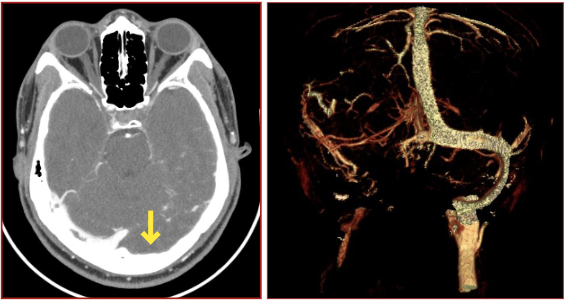

Annals of B-Pod: Dural Venous Sinus Thrombosis

/The headache is the simplest and most complex we see on a daily basis in the ED, but it is important to consider, on both ends, how the coagulation cascade can go awry and be a causative source. Dr. Gawron walks us through a patient presenting with an unprovoked and rather discourteous dural venous sinus thrombosis, its natural history, and appropriate emergent evaluation and management.